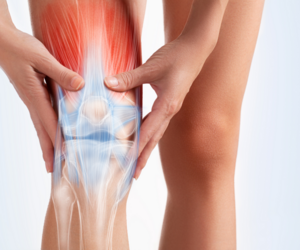

Robotic Knee Replacement Nashik

Utilizing state‑of‑the‑art robotic-assisted systems, Dr. Patil delivers precision knee joint replacement surgery for faster recovery, less pain, and long‑term joint health.